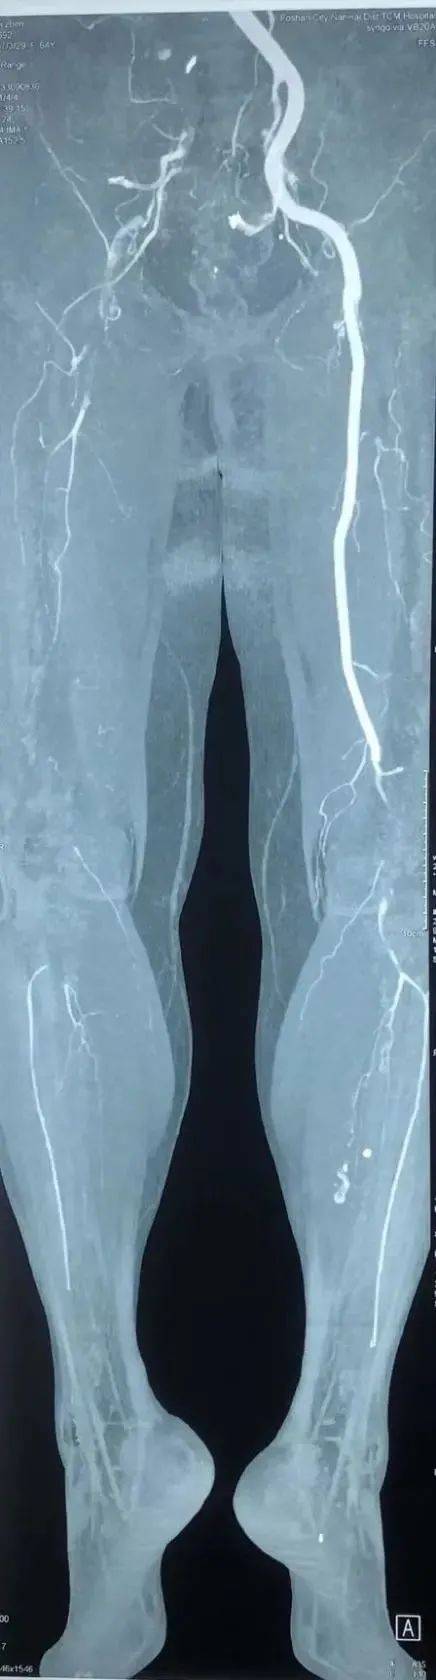

医生查体后发现整个邬女士右下肢皮温凉 , 股动脉、腘动脉、足背动脉搏动消失 。 抽血发现肌红蛋白(肌肉缺血坏死的代谢产物)已高达217.2ug/L(正常值上限61.5ug/L) 。 急诊CTA(CT血管造影)发现整个右下肢血管几乎不显影 , 右髂动脉、股动脉、腘动脉管腔充满了血栓 。

专家团队经右侧腹股沟做一个仅3cm的小切口切开皮肤 , 暴露股总动脉 , 股浅动脉和股深动脉 。 术中切开股总动脉 , 探查发现股总动脉没有血流 , 血栓充满整个管腔 。 于是在X光引导下往股总动脉切口近端送入导丝、5F取栓导管(直径约1.65mm)至髂动脉 , 取出红色长段血栓约40cm;然后往远端送入导丝、4F取栓导管(直径约1.32mm)至腘动脉 , 取出长段血栓约60cm 。